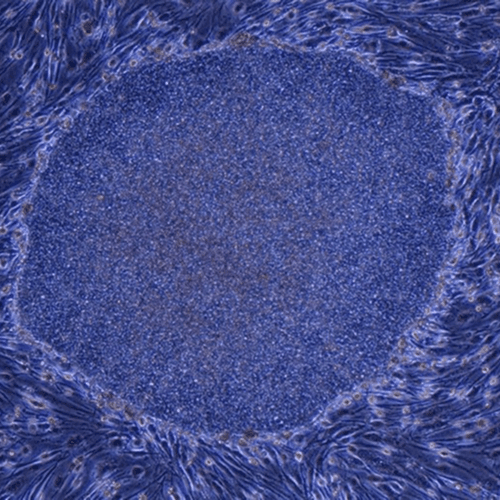

배아줄기세포

정자와 난자가 만나 수정상태로 14일까지를 배아줄기세포라고 하며, 조절 및 윤리 문제로 사용이 금지되어있습니다.